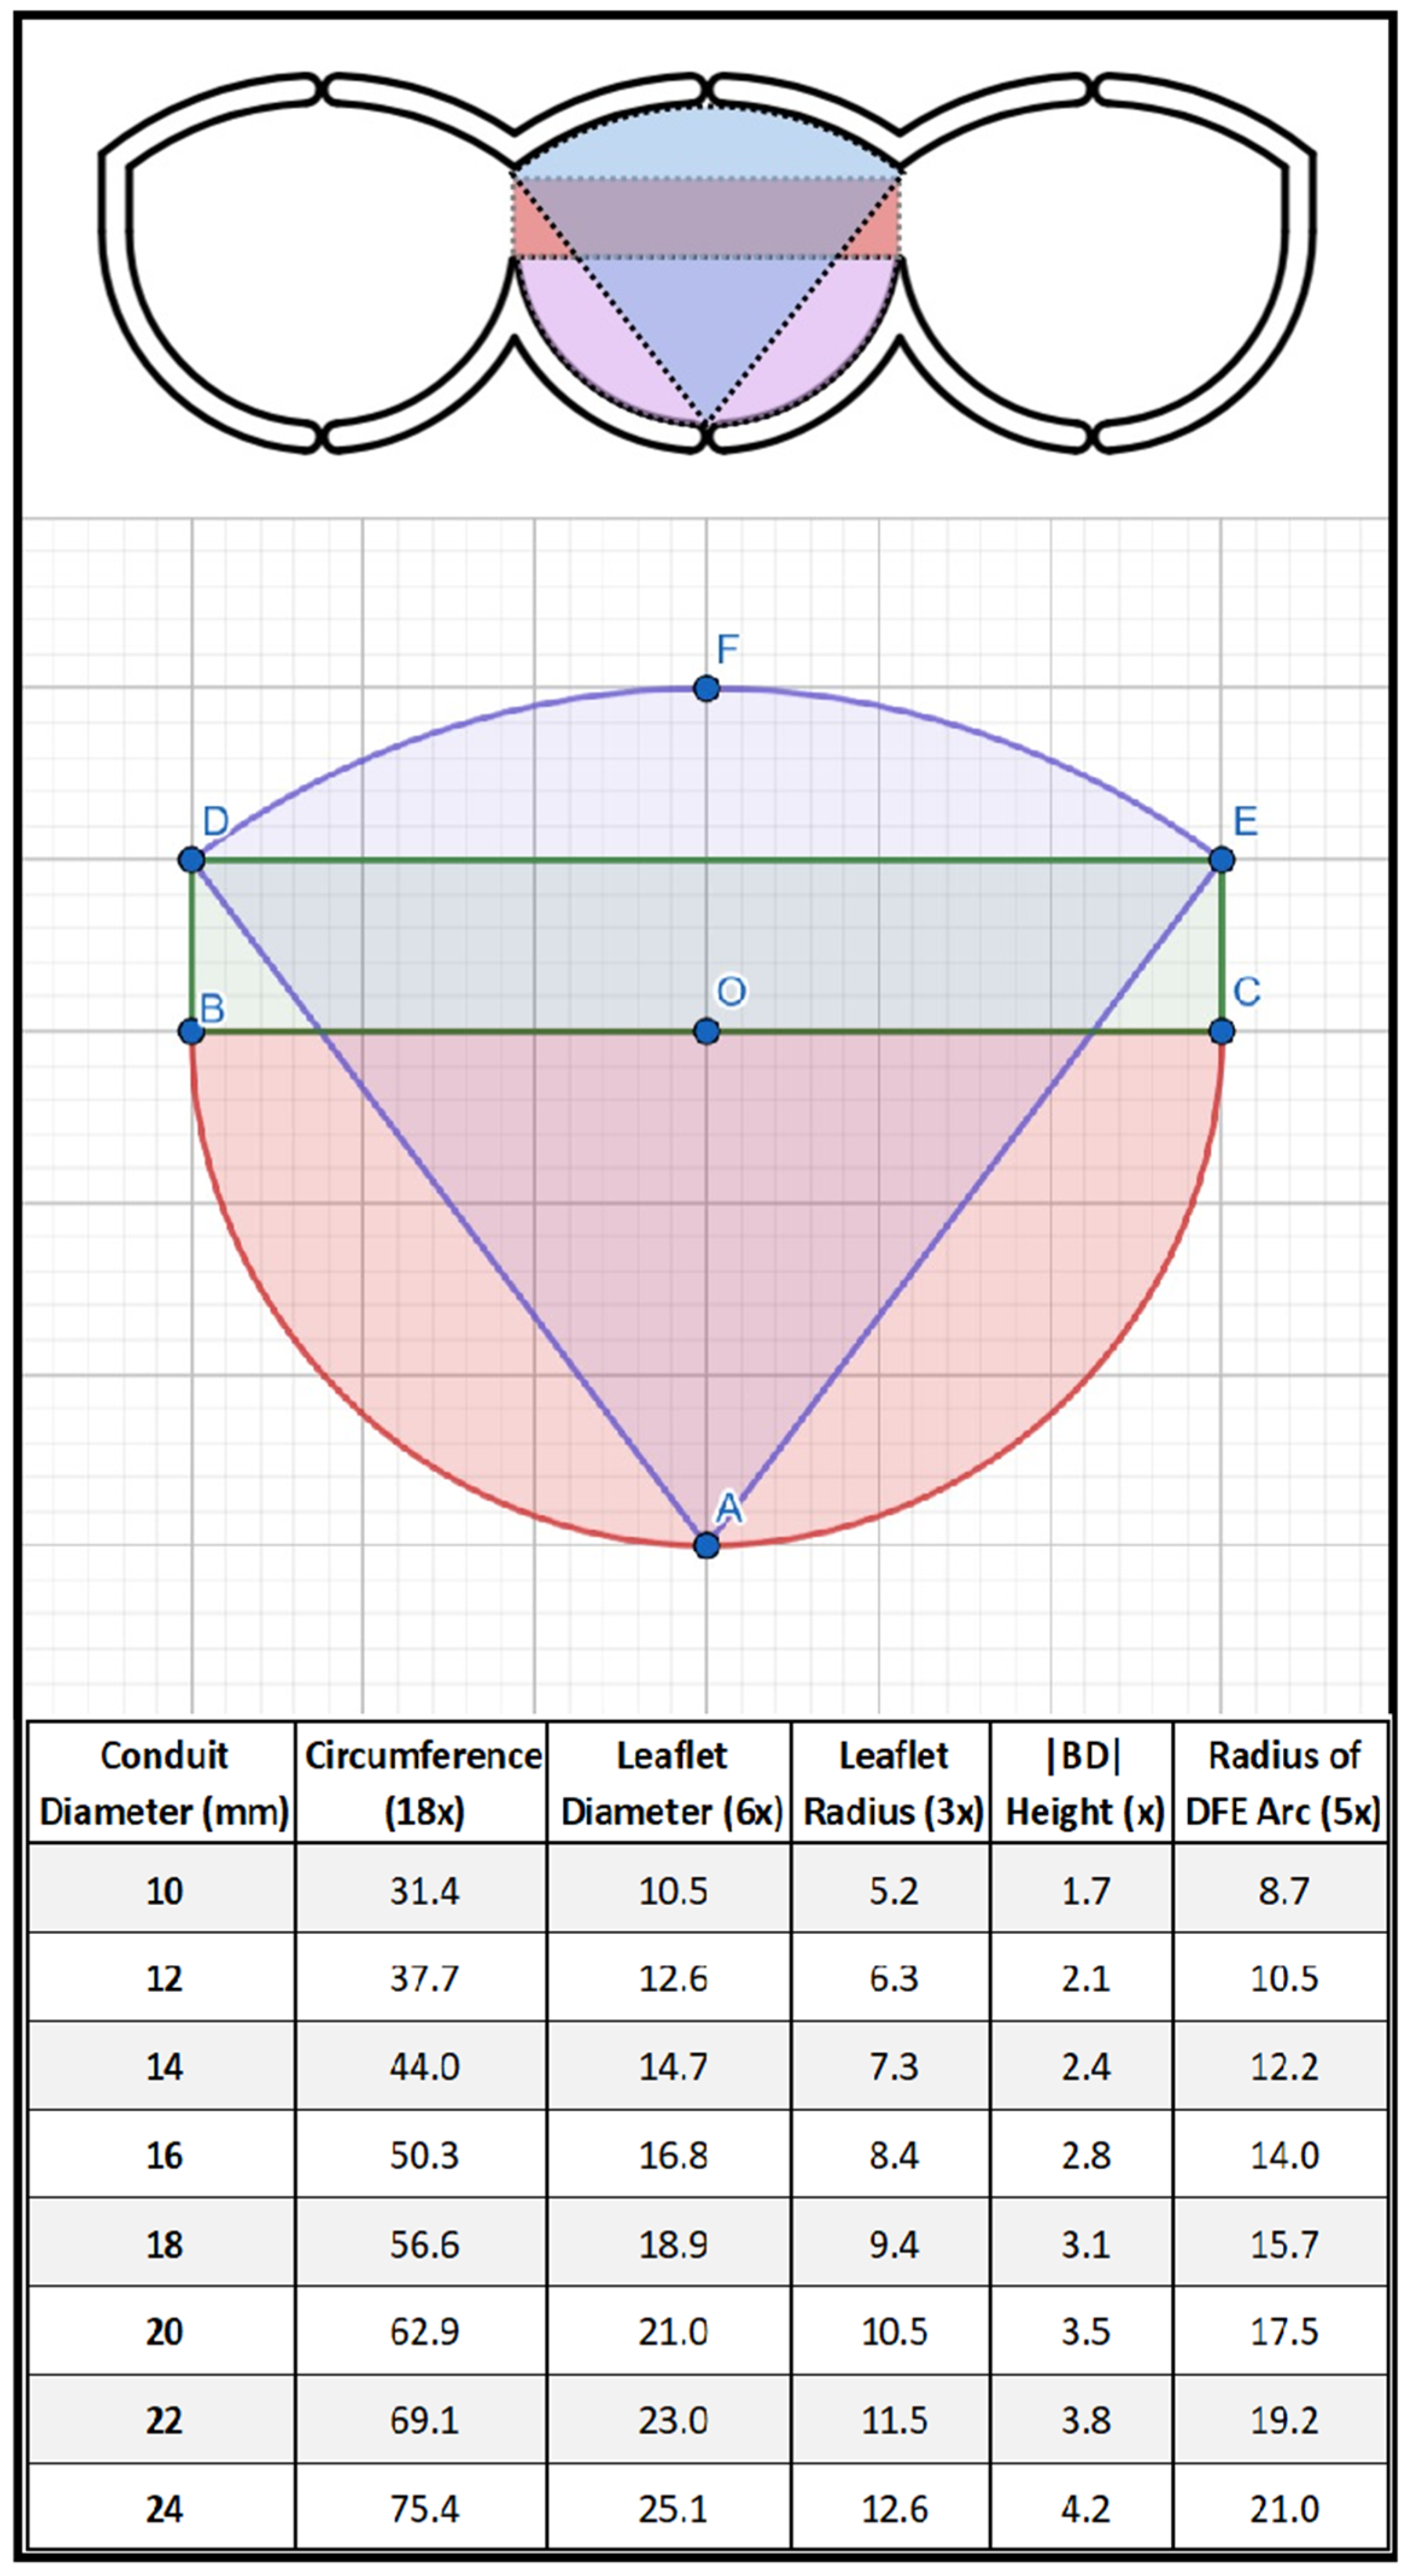

2.1. Surgical Technique